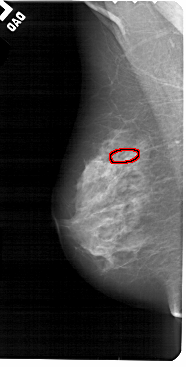

A_1553_1.LEFT_CC

LEFT_CC LINES 5176 PIXELS_PER_LINE 2551 BITS_PER_PIXEL 12 RESOLUTION 43.5 OVERLAY

FILE: A_1553_1.LEFT_CC.OVERLAY

TOTAL_ABNORMALITIES 1

ABNORMALITY 1

LESION_TYPE CALCIFICATION TYPE PUNCTATE DISTRIBUTION LINEAR

ASSESSMENT 4

SUBTLETY 1

PATHOLOGY BENIGN

TOTAL_OUTLINES 1

BOUNDARY